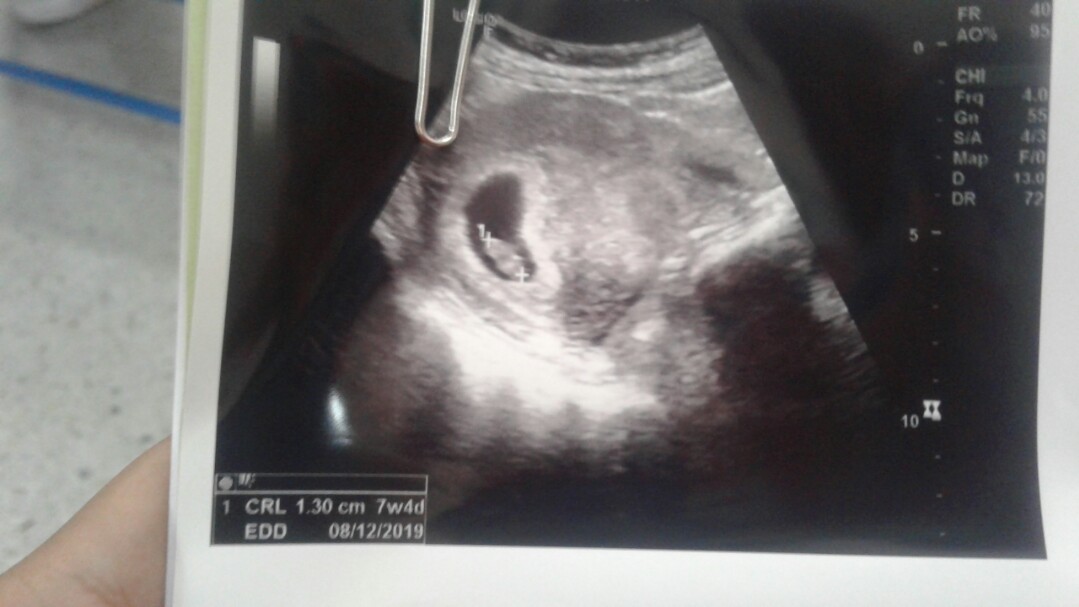

7w4d จ้า